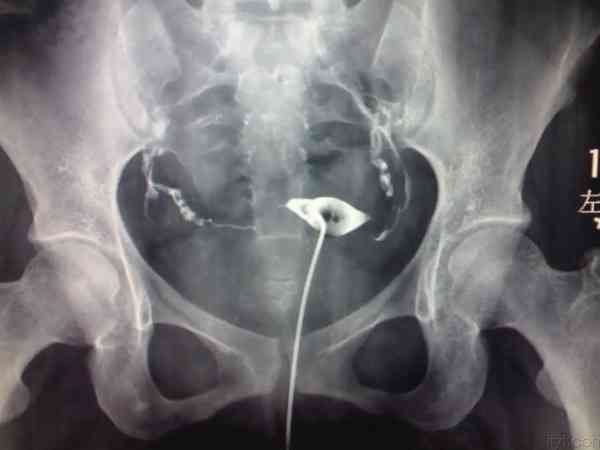

网上1分钟教你看输卵管造影片子主要是通过造影显影图来进行输卵管情况判定的,从图片上可以很直观的看出输卵管通畅、输卵管梗阻、输卵管积水三种情况,其中输卵管梗阻(堵塞)和输卵管积水对于自然备孕是有一定影响的,怀孕几率会有所降低,三种情况具体的判定方法可以参考以下:1、输卵管通畅输卵管通畅在造影片子上可以看到一侧或双侧输卵管伞端有造影剂溢出,盆腔中也会出现造影剂涂抹,之后积极试孕,在排除其他影响不孕不育...